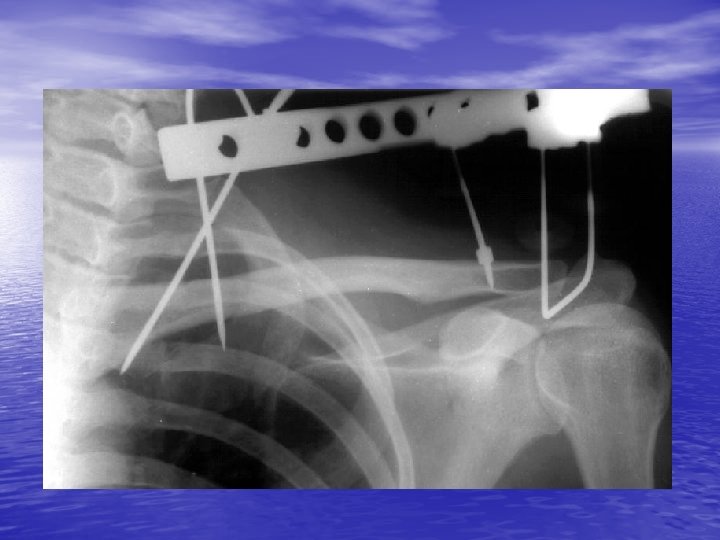

Rockwood type V injury

After 6 weeks